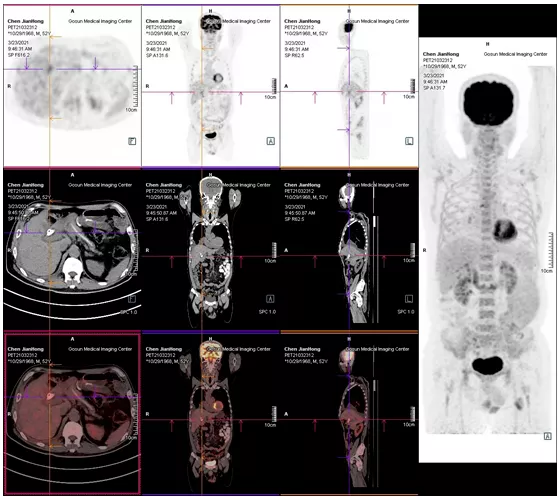

2021年05月 PET/CT檢查結(jié)果

復(fù)查PET-CT提示原術(shù)區(qū)復(fù)發(fā)病灶、肝內(nèi)轉(zhuǎn)移灶、右側(cè)胸膜轉(zhuǎn)移灶控制良好